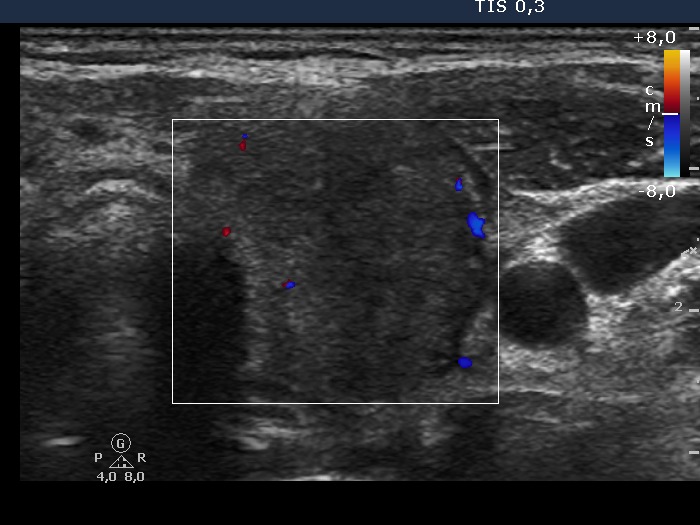

The thyroid contains tiny discrete hypoechogenic areas and presents an average vascularization. |

Final diagnosis: post partum thyroiditis.

We did no give any therapy. 4 months later a hypothyroidism was detected which resolved spontaneously after another 3 months. |